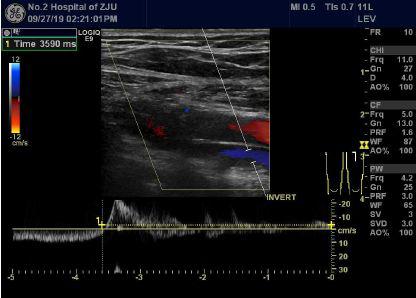

小徐B超图像:股静脉第一对瓣膜在屏气时可见返流信号,提示双侧下肢深静脉瓣膜功能不全